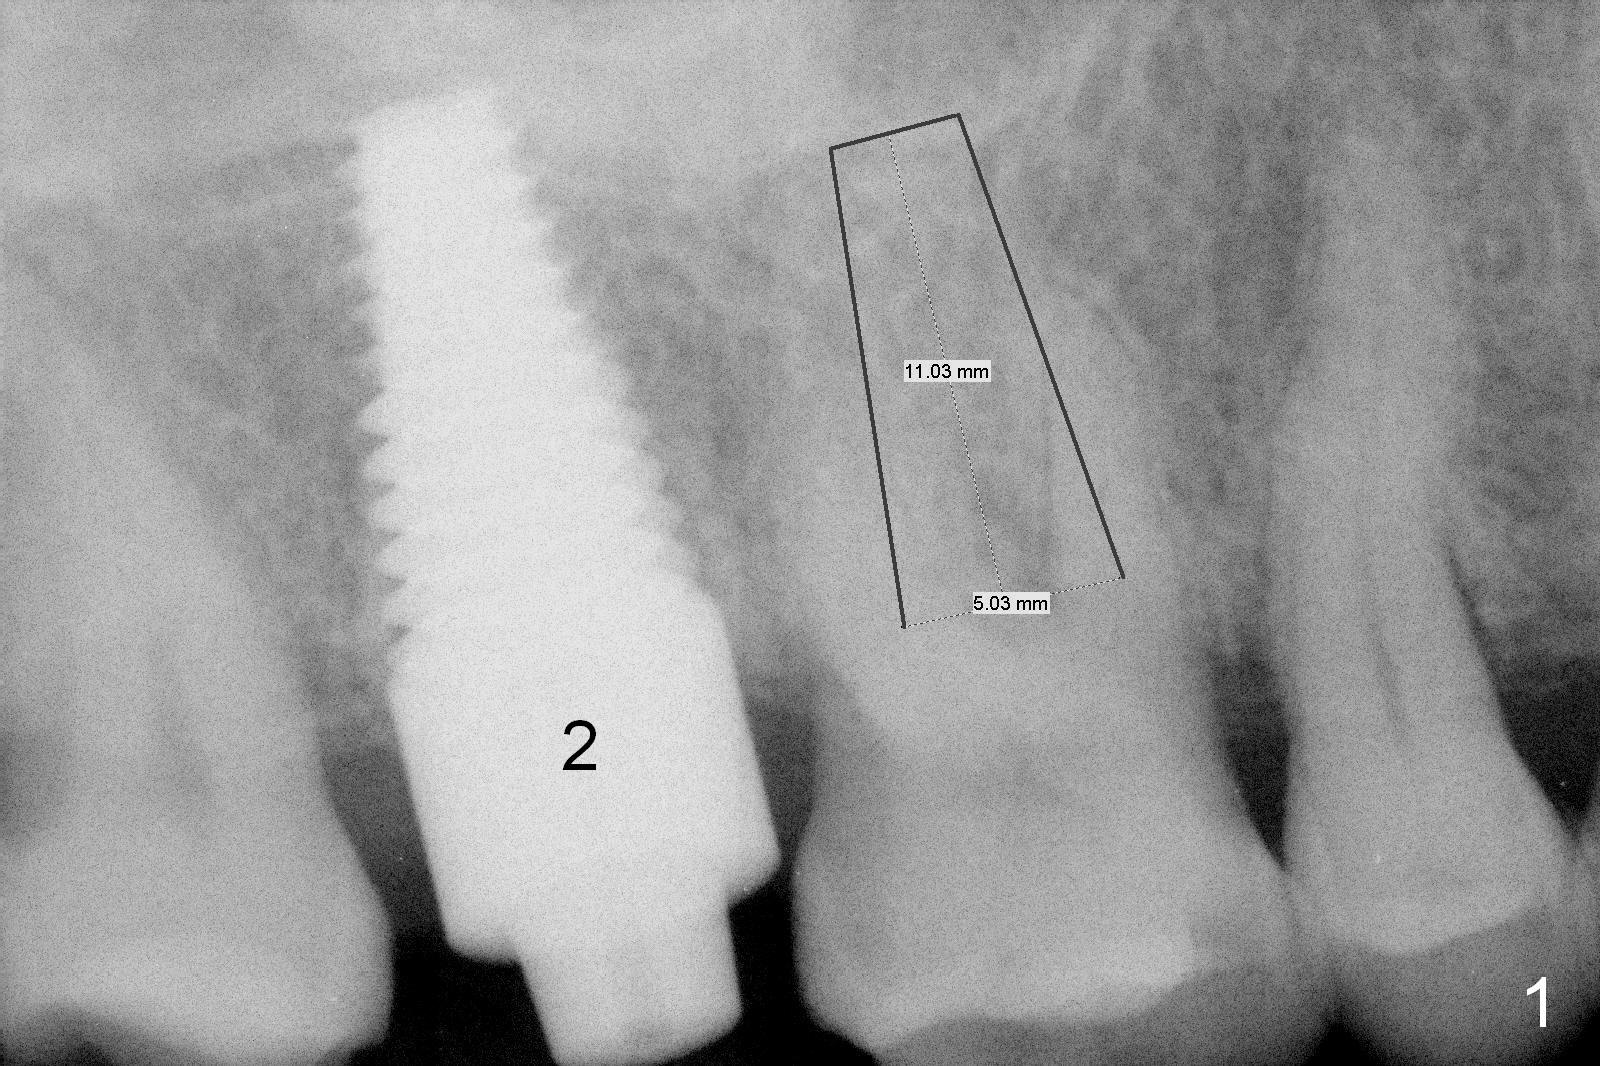

Provisional to Support Buccal Gingiva A 67-year-old woman with Parkinson disease has sign of several tooth chip. The tooth #3 fractures mesiodistally 1 year 7 months post cementation of the crown at #2. Take photos to show the crack line. After extraction (Metronidazole), explore the socket to determine bone integrity. If the septal crest is wide, use 1.6 drill (take 1st PA PRN) and Marking Bur before 4.3 mm Magic Drill. Otherwise use sequential drills, or alternating with Magic Expander if the bone is soft. No matter whether IBS (Fig.1) or Tatum (Fig.2) implant is placed, an immediate provisional will be fabricated so that the margin of the provisional is subgingival to prevent buccal plate collapse and bone graft leakage. Return to